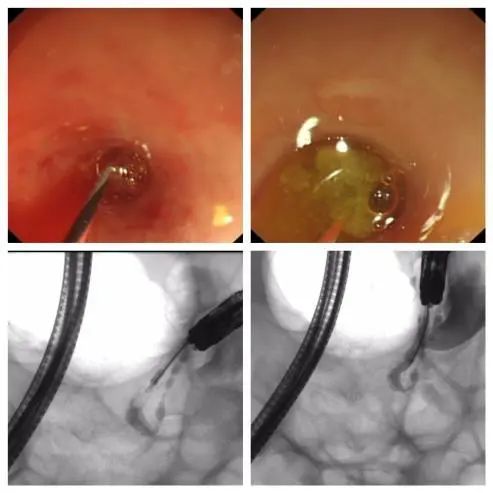

通过短镜操作孔道置入子镜,刘鹏飞主任操作子镜进入阑尾腔,阑尾腔中段见管腔变窄,狭窄处见多枚粪石嵌顿。

集中清理

经子镜以生理盐水反复冲洗,清理出较多脓液、大量粪渣,子镜越过粪石抵达阑尾盲端,见阑尾远段黏膜广泛苍白、水肿,局部黏膜呈紫红色,黏膜表面有大量絮状脓苔附着,与超声术前判断完全符合。

经子镜反复冲洗阑尾腔,由操作孔道置入超细取石网篮,直视下兜取粪石,收束网篮,固定后随子镜退出阑尾腔。

空中预警

在 X 线动态监测见粪石清除,造影提示阑尾腔通畅,造影剂无外渗。